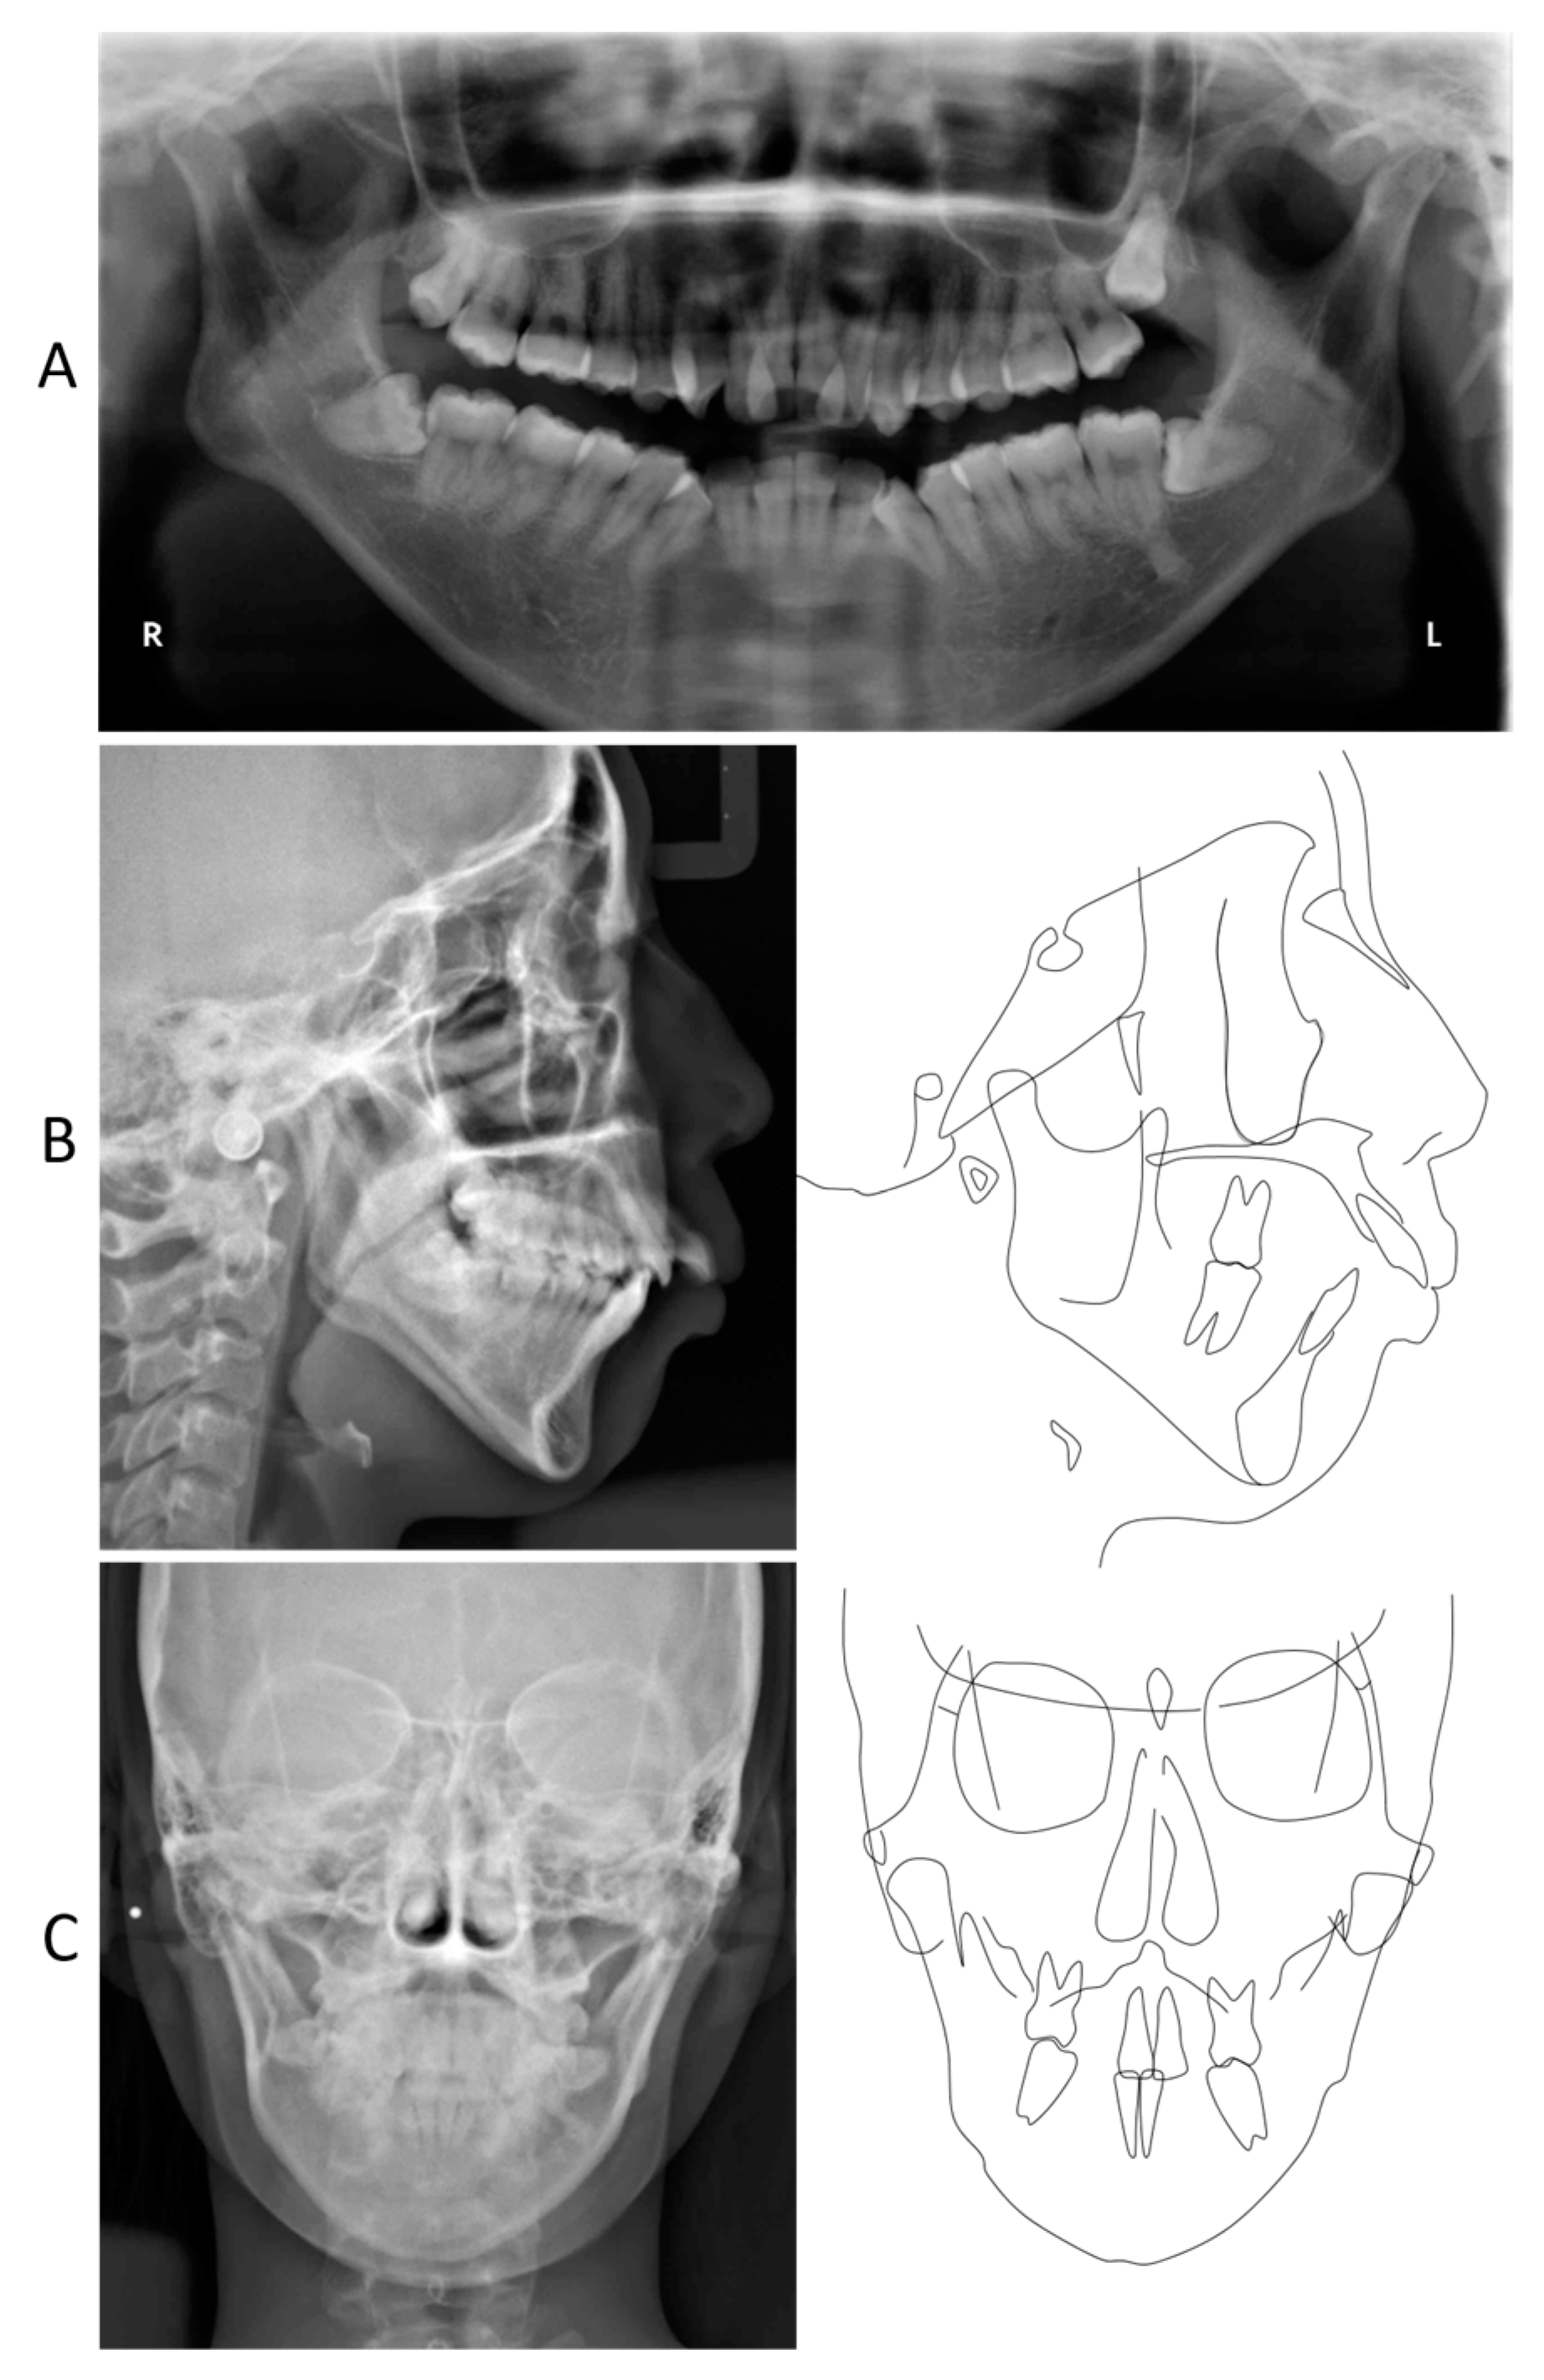

2. Detailed Case Description

2.3. Treatment Progress